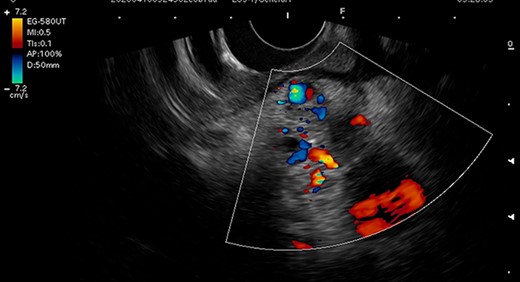

Endoscopic ultrasonography image. Endoscopic ultrasonography showed tortuous vessels and low echoic lesions in the pancreas head, and no findings suspicious of malignancy.